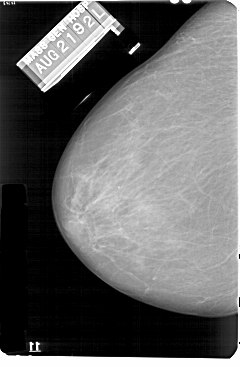

A_1131_1.LEFT_MLO

DATE_OF_STUDY 21 8 1992

PATIENT_AGE 86

FILM_TYPE REGULAR

DENSITY 2

DATE_DIGITIZED 18 6 1998

DIGITIZER HOWTEK 43.5

LEFT_MLO LINES 5491 PIXELS_PER_LINE 3766 BITS_PER_PIXEL 12 RESOLUTION 43.5 NON_OVERLAY